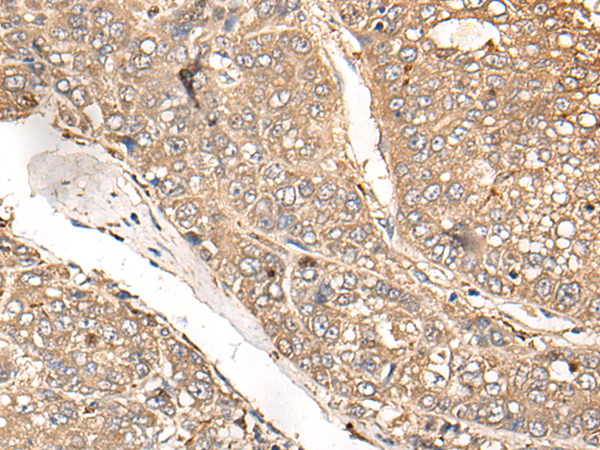

(Immunohistochemistry of paraffin-embedded Human liver cancer tissue using MAGEA1 Polyclonal Antibody at dilution of 1:25(×200))